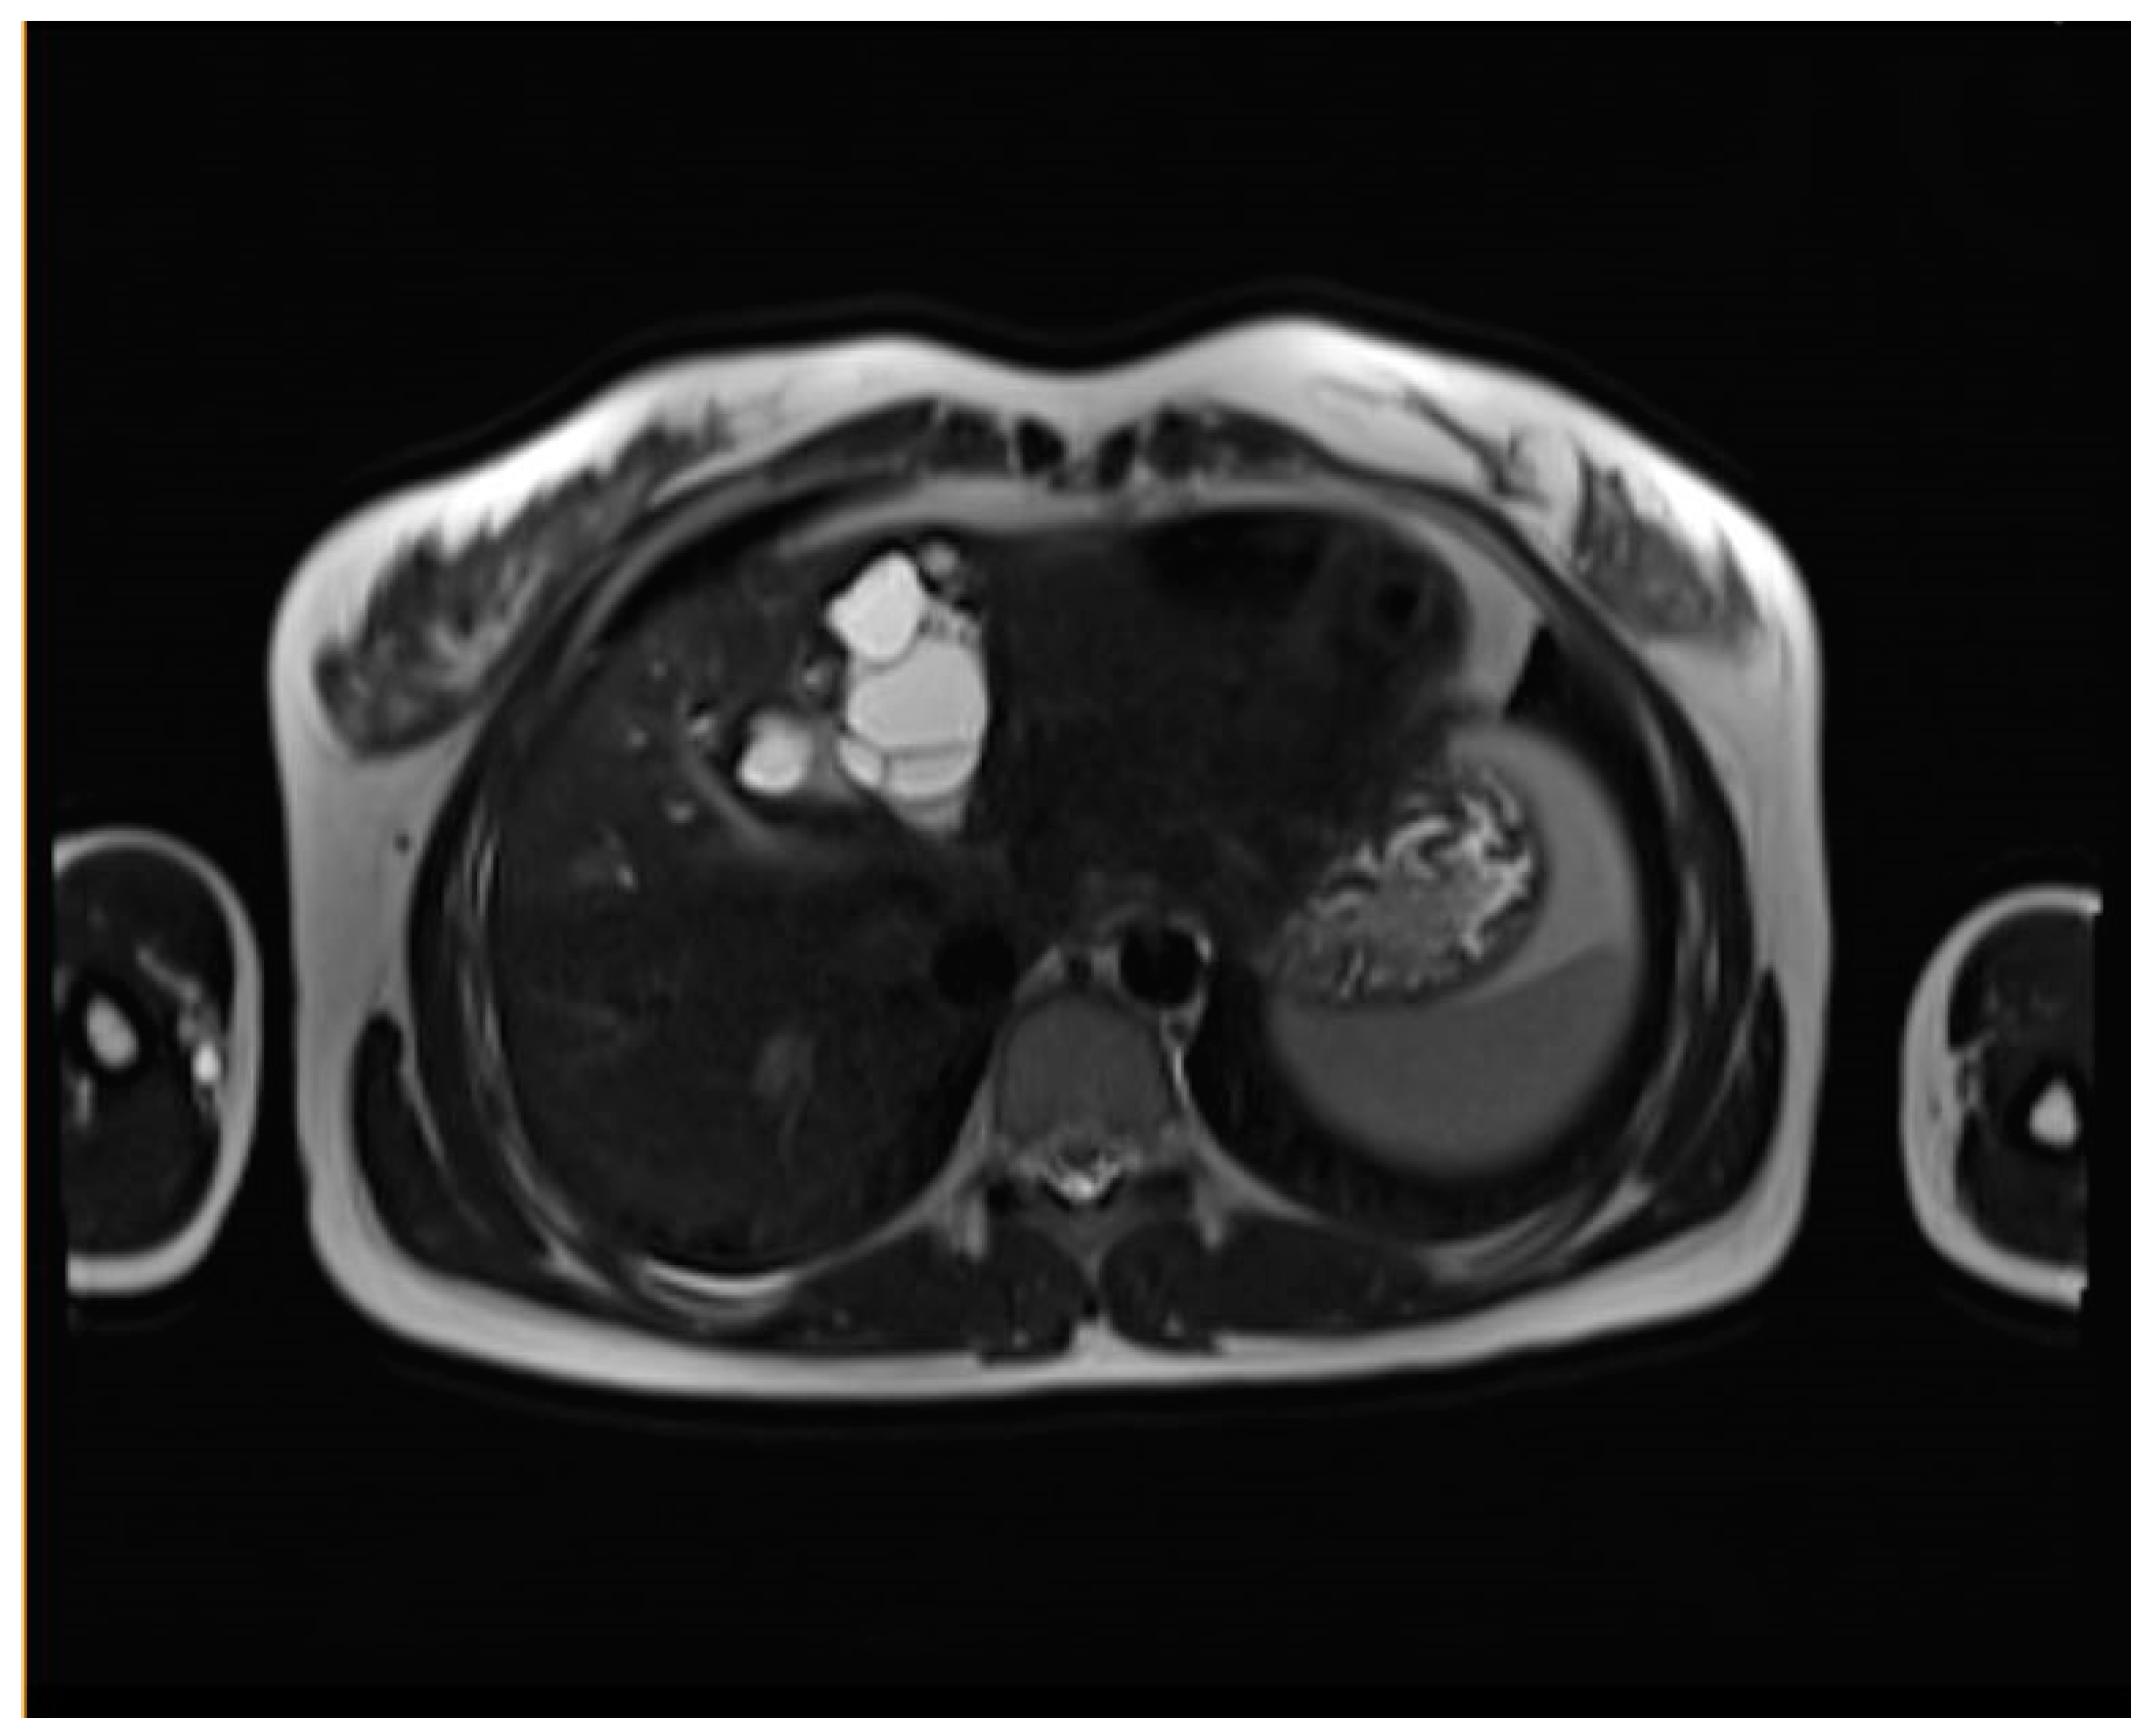

| CE1 (Simple cyst) | Well-defined, unilocular cyst with a peripheral capsule, hypointense on T2WI, possible rim sign. Hyperintense hydatid matrix on DWI and ADC. | Unilocular anechoic cyst with possible rim sign and internal echoes (hydatid sand, snowflake sign) seen after repositioning. |

| CE2 (Cyst with daughter cysts and matrix) | Multicystic mass with septa (wheel-spoke pattern), daughter cysts are hypointense or isointense compared to the mother cyst on both T1WI and T2WI. | Well-defined cyst with multiple internal septations and daughter cysts, described as honeycomb or rosette appearance. |

| CE3A (Transitional) | Detachment of laminated membranes, with a floating water lily sign or serpent sign. Daughter cysts may be visible in the matrix. | Internal floating membranes or detached laminated membranes (water lily sign). |

| CE3B (Transitional; daughter cysts within solid matrix) | Solid matrix with visible daughter cysts; signal intensity varies depending on the proteinaceous content of the cyst. | Similar to CE3A, but daughter cysts are present within a solid matrix, often with calcification. |